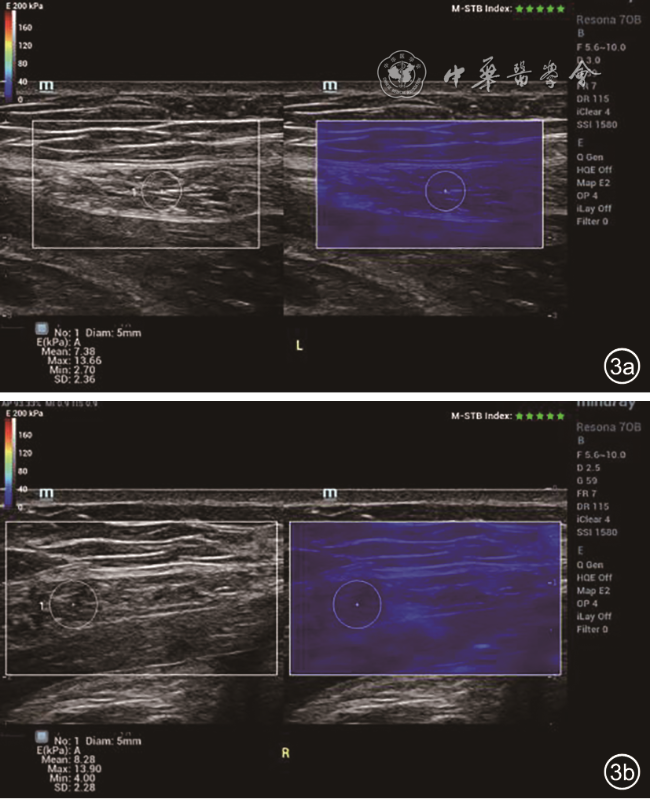

图3 22岁未育女性,脐上5 cm水平左侧腹直肌剪切波弹性成像(SWE)定量测量,Emean=7.38 kPa,Emax=13.66 kPa,Emin=2.70 kPa(图a);右侧腹直肌SWE定量测量,Emean=8.28 kPa,Emax=13.9 kPa,Emin=4.0 kPa(图b)